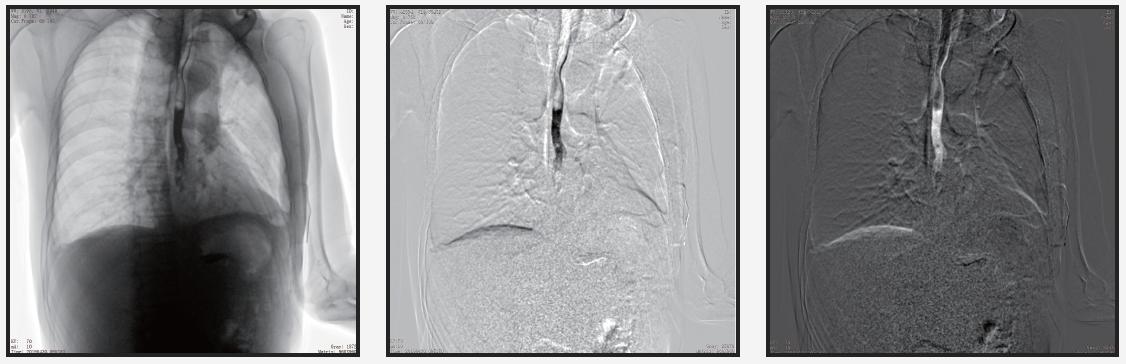

自主研发的组织均衡技术

人体图像通过组织均衡后,图像细节更突出,肺纹理末端细小血管及骨骼的纹理、肌肉层次等均可清晰显示。